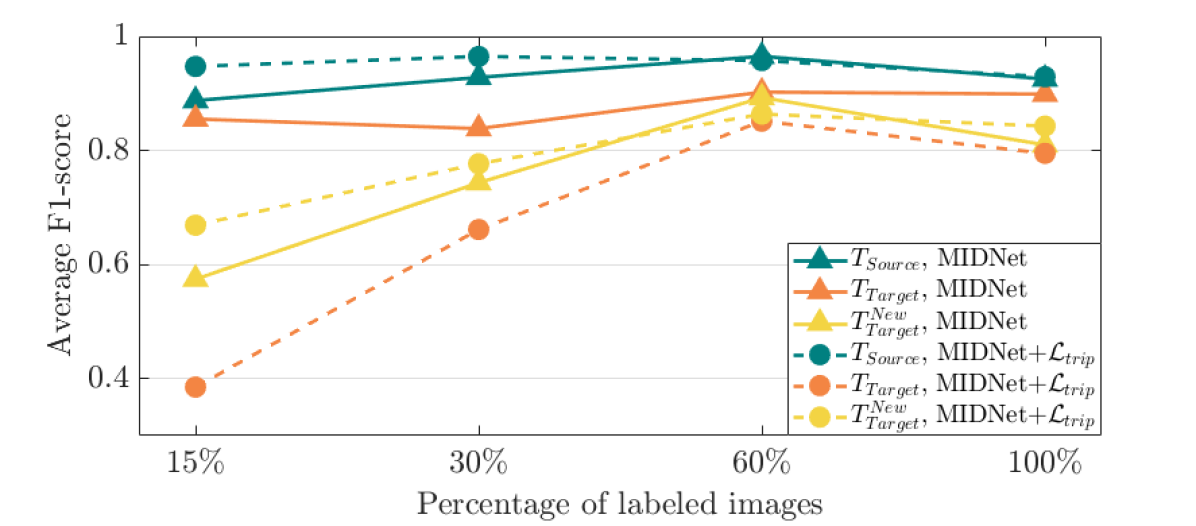

To explore the importance of labeled data, we evaluate the performance of MIDNet and MIDNet+ based on using and labeled data during training. Fig. 9 (a) shows the average F1-score on three groups of test data. From this figure, we observe that the classification performance improves with increasing labeled data.

From Fig. 9 (b), we observe that classification performance improves with the increase of labeled data in most cases. However, the performance reaches its peak after a certain percentage of labeled data is added. For example, the peak point is in this experiment.

To explore the importance of labeled data, we evaluate the performance of MIDNet based on using and labeled data during training. Fig. 15 shows the average F1-score of these experiments on three groups of test data. From this figure, we observe that the classification performance only slightly improves with increasing labeled data. This indicates that MIDNet is capable of achieving expected performance with sparsely labeled data. Additionally, excessive labeled data may lead to increased class imbalance. This may result in decreased classification performance as shown in Fig. 15 when the percentage of labeled training data increased from (i.e., all classes contain the same number of labeled images: 4294 images) to (i.e., Digit 1: 10768 labeled images vs. Digit 5: 4336 labeled images).